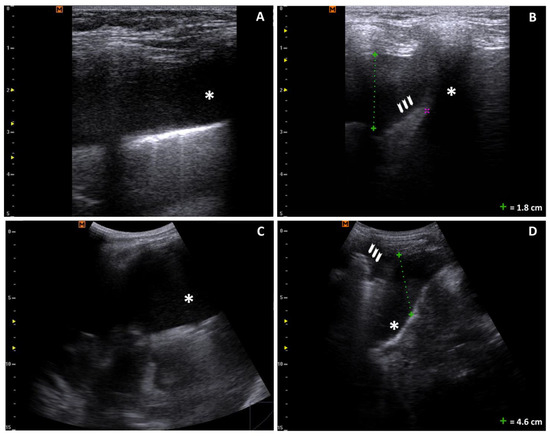

Upon admission to our PED, a complete POCUS was performed, which showed bilateral pleural effusion, mild pericardial effusion, and ascites without other signs of pulmonary parenchymal or cardiac involvement (Figure 1, Figure 2 and Figure 3). Bedside focused cardiac ultrasonography (FoCUS) allowed us to exclude systolic dysfunction or cardiac tamponade.

Figure 1. Bilateral pleural effusion: (A,B) longitudinal scan of the right lung with a linear probe showing a 1.8 cm anechoic pleural effusion (*) and underlying atelectasic lung (arrowheads); the purple cursor is a measurement typo; (C,D) longitudinal scan with a convex probe showing massive anechoic pleural effusion (*) and underlying atelectasic lung (arrowheads).